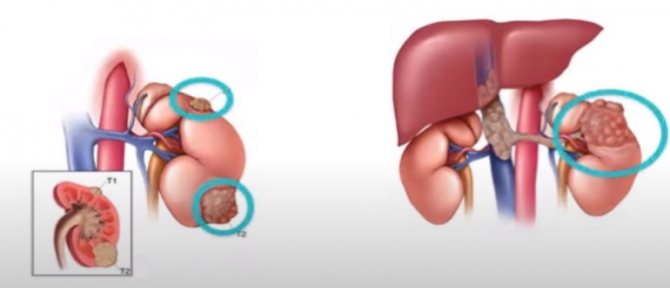

Понимание кавернозного туберкулеза почки

Раздел: Мудрость в деталях